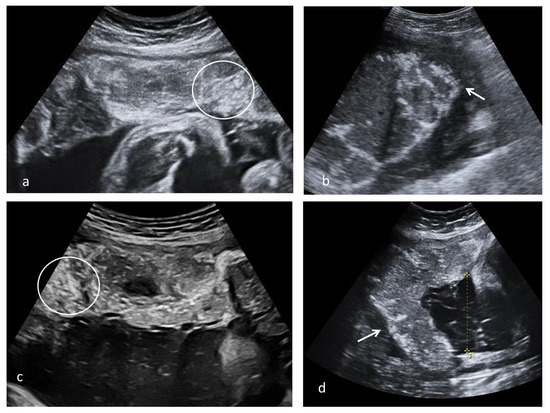

The pathology exam found 9 (39.1%) small for gestational age (GA) and 2 (8.7%) abnormally large for GA placentas. It was also found that 60% of placentas from patients with second trimester viral infection were small for GA. Macroscopic examination revealed a peripheric white annular border and circummarginate membrane insertion (Figure 4f).

Figure 4.

Stem villi perivillous fibrin deposits pattern (arrows–circumferential homogenous pink material around stem villi). (a)—focal pattern, most of the stem villi observed are not surrounded by perivillous fibrin deposits (Hematoxylin-Eosin, 2×). (b)—frequent pattern, a group of large stem villi and several smaller stem villi surrounded by perivillous fibrin deposits (Hematoxylin-Eosin, 2×). (c,e)—images from different cases presenting perivillous fibrin depositions around stem villi (c)—Hematoxylin-Eosin, 4× (d)—Hematoxylin-Eosin, 10×, (e) perivillous fibrin depositions around the stem villi Hematoxylin-Eosin, 10×, (f) fresh macroscopic, the circummarginate appearance of the placenta.

Maternal vascular malperfusion lesions were noted in all cases, predominantly distal villous hypoplasia and accelerated villous maturation. Fetal vascular malperfusion lesions were less encountered. We rarely found focal calcifications (13%), chorioangiosis (8.7%), and inflammatory lesions (8.7%).

We noted a particular pattern of fibrin deposits around stem villi, represented by various amounts of continuous circumferential perivillous fibrin deposits. When few stem villi were involved the lesion was considered focal, and if most villi were affected, the lesion was considered frequent (Figure 4 and Table 3).